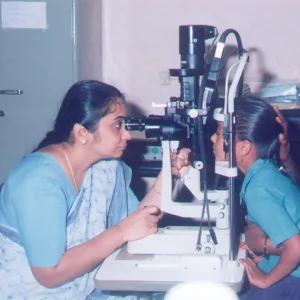

Community Ophthalmology

Established to address eye health challenges within rural and urban populations, these programs focus on preventing avoidable blindness and improving the quality of life for patients with limited access to healthcare

- Outreach Camps